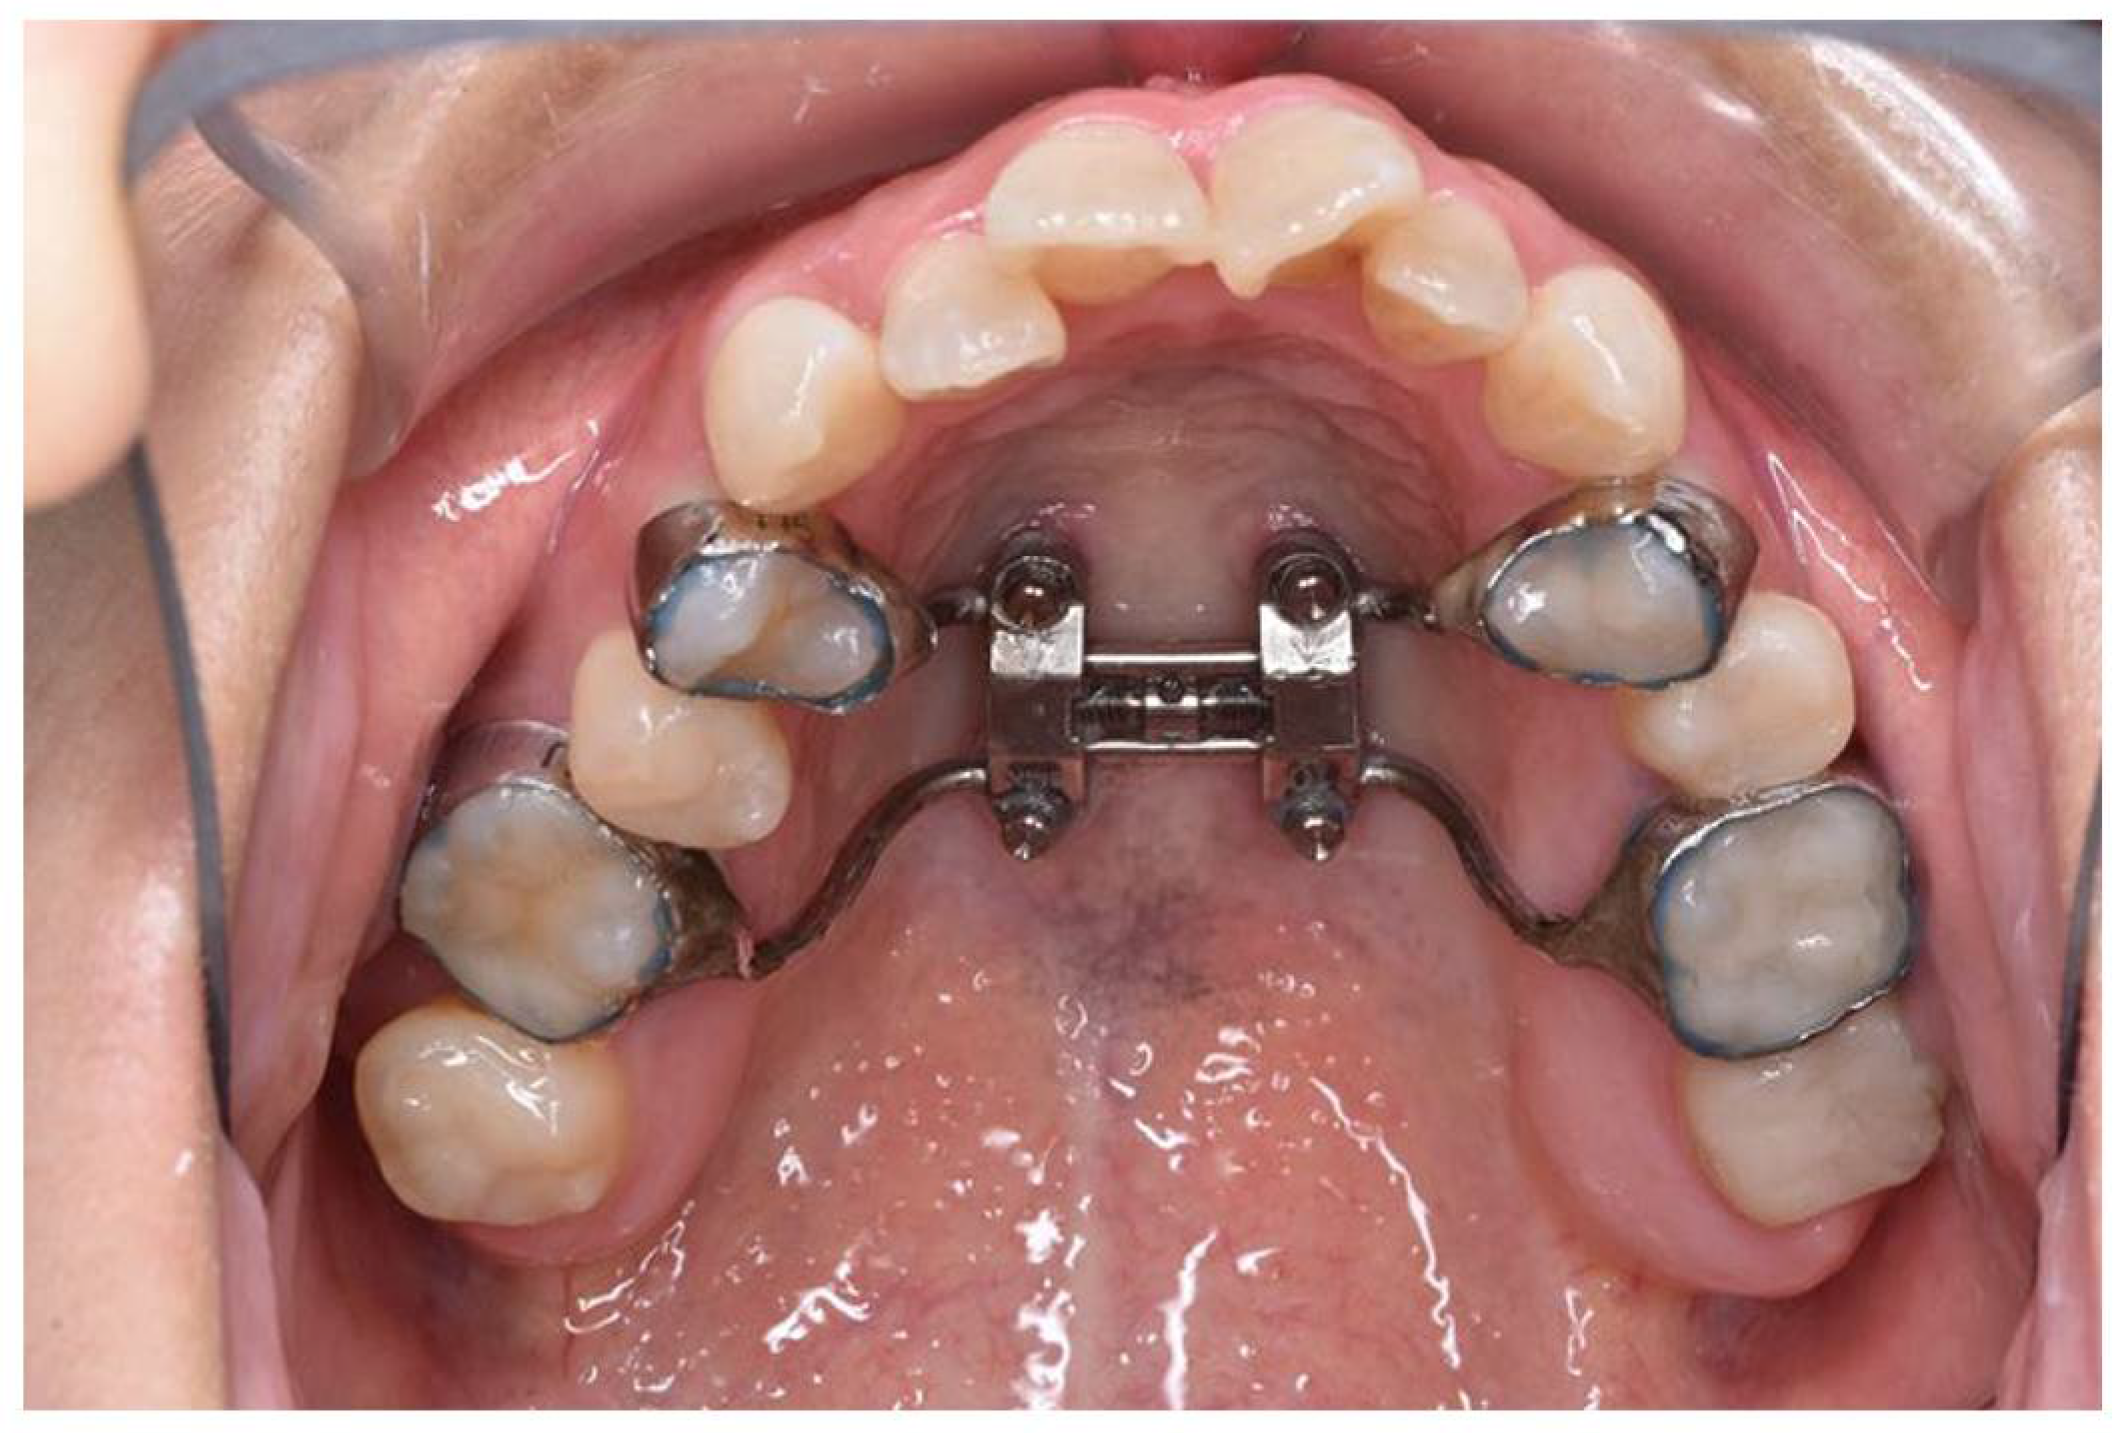

The appliance was fabricated with orthodontic bands on the first premolars and first molars. It features four holes for orthodontic screws, which were 11 mm long and inserted into the bicortical plates of the maxillary bone near the midpalatal suture.

The MARPE device (M.S.E., Maxillary Skeletal Expander, Forest-One Co., cChiba, Japan) was placed by the orthodontist. It was fabricated with orthodontic bands on the first premolars and first molars and designed with four holes for orthodontic screws. The expansion appliance was secured using 11 mm long screws inserted into the bicortical plates of the maxillary bone near the midpalatal suture (

Figure 2). Subsequently, orthodontic treatment was initiated, and the patient also began maxillary expansion.